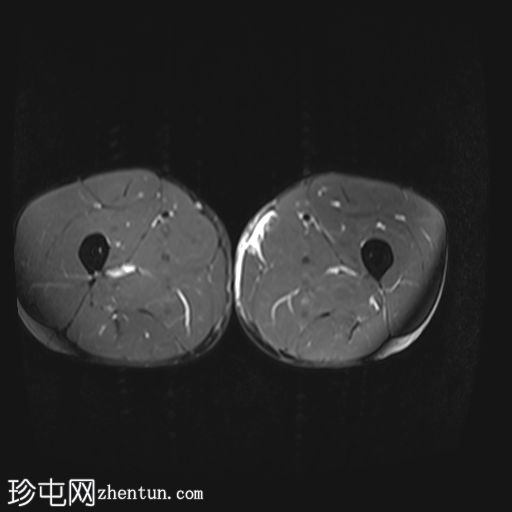

轴向

T1

收肌长肌腱从耻骨起点完全撕脱,可见充满液体的间隙(4毫米),肌腱近端回缩。

相关的肌内水肿累及收肌长肌、短肌和耻骨肌,筋膜间液沿股薄肌向内侧延伸。

MRI 表现与收肌长肌腱从起点撕脱并远端回缩相符,可见充满液体的间隙、筋膜间液和肌肉拉伤。

根据英国田径协会肌肉损伤分类(BAMIC),该损伤被归类为 4c 级。